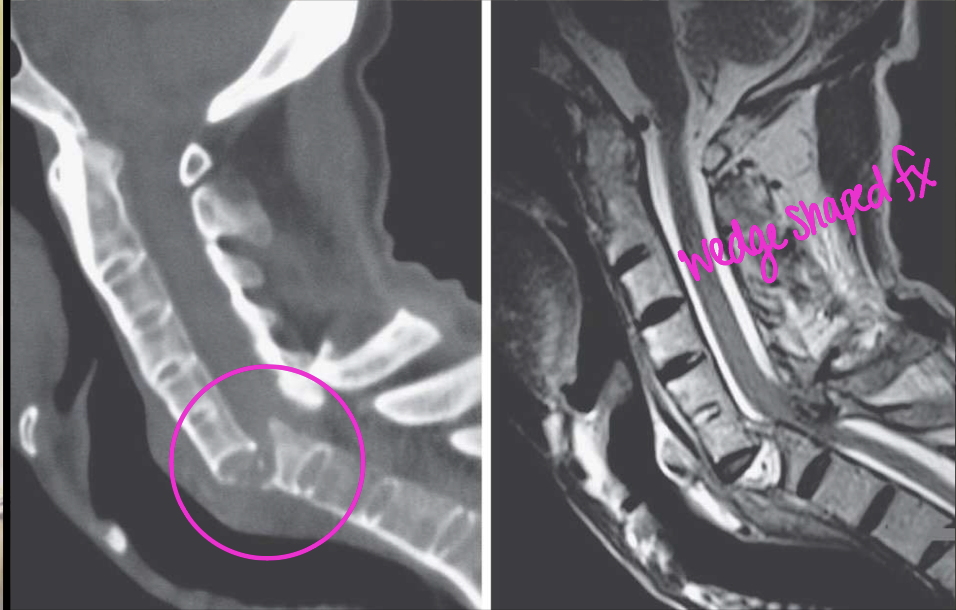

AS spinal findings are not enough to dx, what additional information/imaging do you need to be able to diagnosis AS

erosions of SI

What three DDx could you give this patient

OPLL

AH

OA/DDD